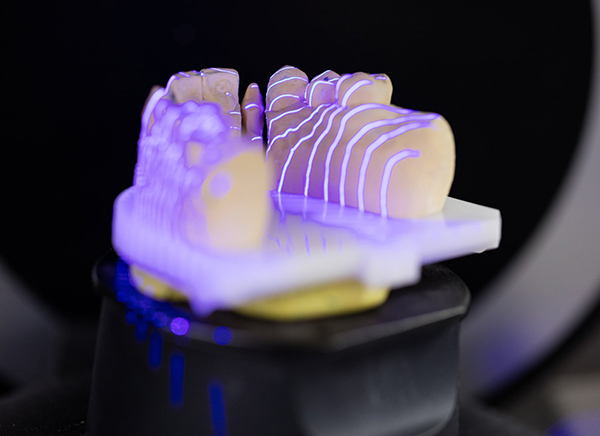

智能种植

Intelligent

implant -

智能种植,用科技遇见最美笑容

如何减少种牙恐惧,增加治愈信心

如何缩小手术创伤,增加患者舒适感受

如何节约时间成本,不再让人为种牙奔波反复

智能种植,给了我们全新的答案……